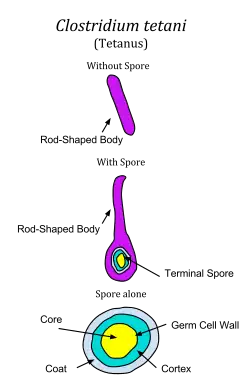

| Clostridium tetani forming spores | |

Clostridium tetani is a common soil bacterium and the causative agent of tetanus. Vegetative cells of Clostridium tetani are usually rod-shaped and up to 2.5 μm long, but they become enlarged and tennis racket- or drumstick-shaped when forming spores. C. tetani spores are extremely hardy and can be found globally in soil or in the gastrointestinal tract of animals. If inoculated into a wound, C. tetani can grow and produce a potent toxin, tetanospasmin, which interferes with motor neurons, causing tetanus. The toxin's action can be prevented with tetanus toxoid vaccines, which are often administered to children worldwide.

Upon exposure to various conditions, C. tetani can shed its flagellums and form a spore.[1] Each cell can form a single spore, generally at one end of the cell, giving the cell a distinctive drumstick shape.[1] C. tetani spores are extremely hardy and are resistant to heat, various antiseptics, and boiling for several minutes.[2] The spores are long-lived and are distributed worldwide in soils as well as in the intestines of various livestock and companion animals.[3]